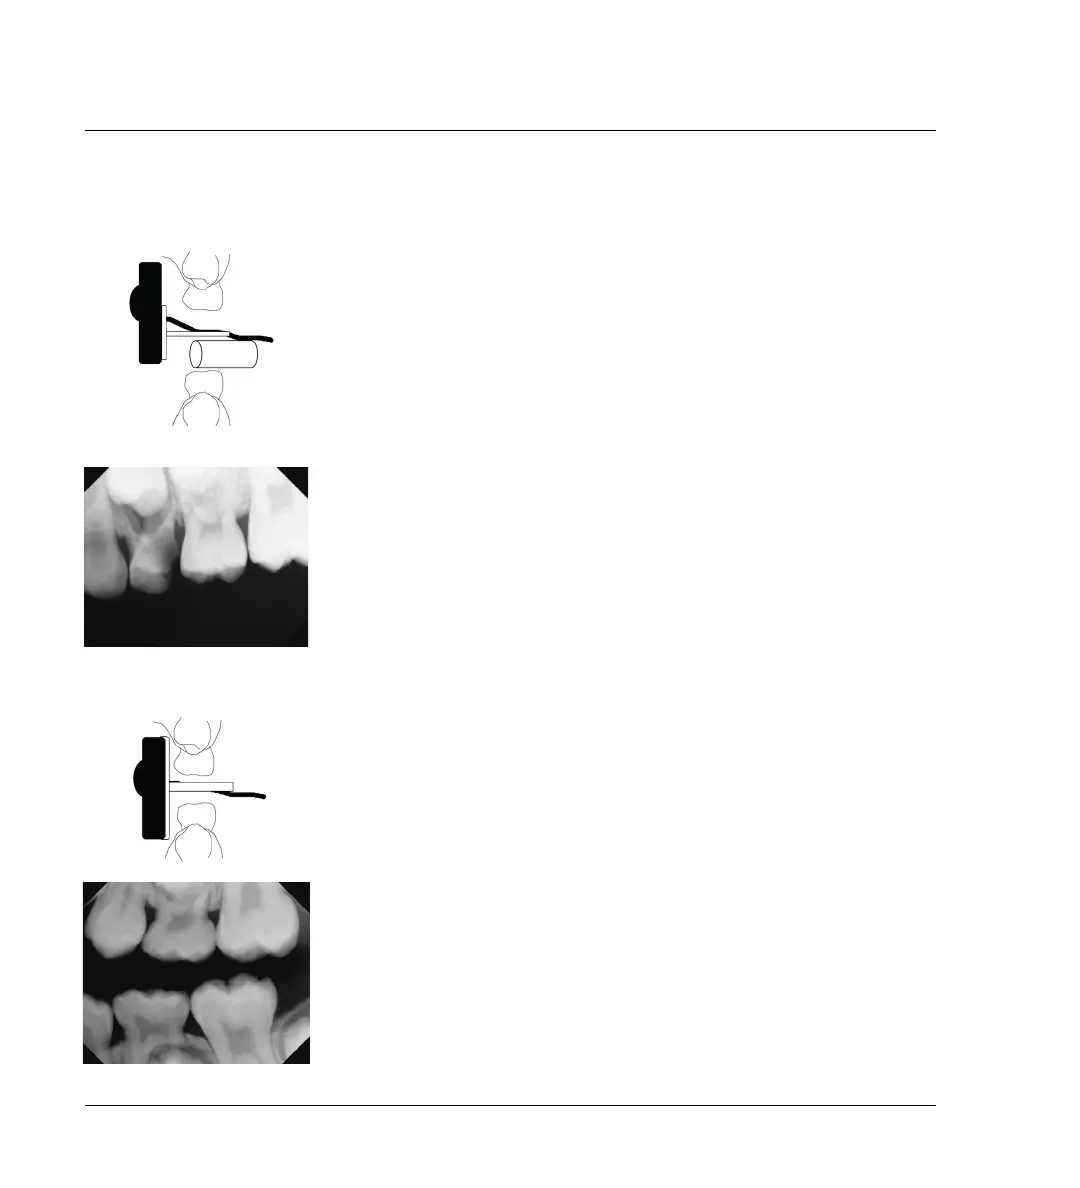

3.4.1 Periapical X-rays

3.4.2 Bitewing X-rays

When you are taking bitewings and your goal is to see the crowns of the pri-

mary teeth, you will find that often the child will not need to close all the

way. Place the sensor in the center of the palate first. (When the sensor is

placed in the mandible, the child is more likely to try to manipulate the sen-

sor.) Next, have the child close down an appropriate amount. Then, ask the

child to focus on saying “eeeeee” to allow better vision into the mouth and

aid in producing a well-placed image.

Use the bitewing biteblock, with or without the ring and bar. If this is not

possible, using a bitewing tab, cover, sticky or foam.